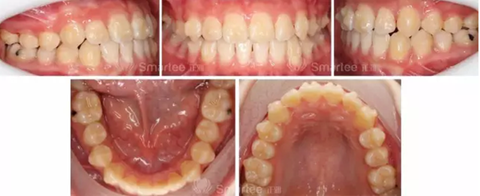

(矯治前后反饋情況對比)

病例小結(jié)

1)隱形矯治器配合牙合墊附件,對于前牙反牙合的解除起到了重要作用。

2)通過優(yōu)化附件的使用,很好的整平了spee曲線。

3)通過增加控根附件,11、21做到了良好的控根移動(dòng)。